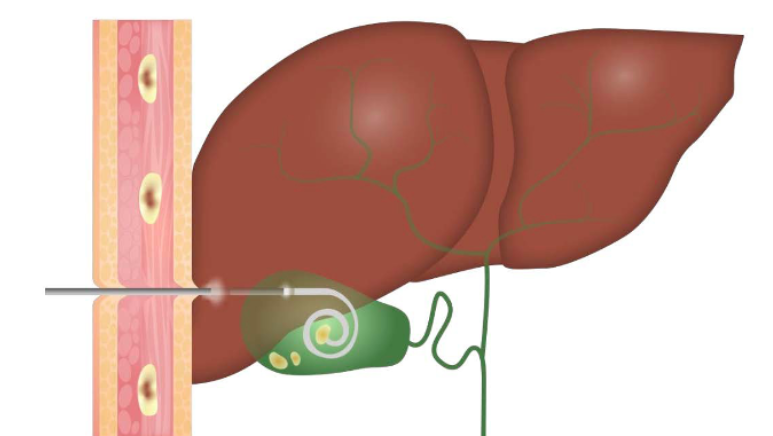

Biliary decompression is the cornerstone of management for cholangitis and should be performed urgently. The two main approaches are endoscopic retrograde cholangiopancreatography (ERCP) and percutaneous transhepatic drainage.

(a) ERCP — endoscopic approach for biliary drainage and stone removal

(b) Percutaneous transhepatic drainage — alternative approach when ERCP is not feasible

Figure 15: Biliary drainage procedures used in the management of cholangitis.